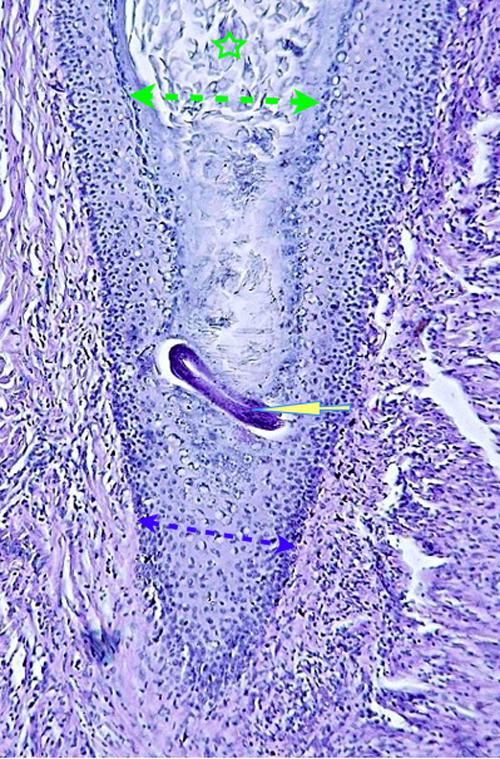

Photo 2 (Hémalun Eosine X 100) peau velue : Vue rapprochée de la Photo 1,

sur un infundibulum folliculaire criblé de pustules pariétales microloculaires.

On note une hyperkératose orthokératosique de l’infundibulum adjacent.

Légendes de la Photo 2 :

- Double flèche bleue pointillée : grand axe des infundibula folliculaires

- Double flèche verte : derme

- Étoiles rouges pleines : erreur (!)

- Ovales jaunes : pustules folliculaires pariétales (folliculite murale)

- Étoiles vertes évidées : lumière des follicules pileux, à gauche parakératosique, à droite orthokératosique